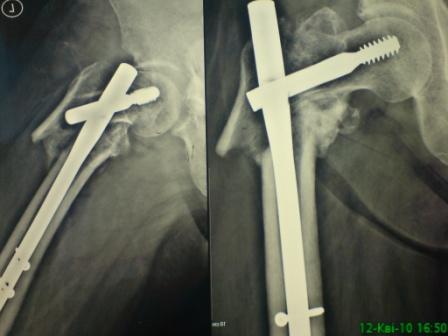

[Ortho] неправильно-срастающийся черезвертельный перелом после Gamma-long(больше разрешение)